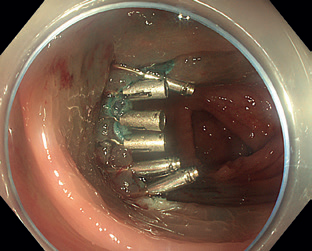

Obr. 13 Částečně disekovaná léze.Endoskopická transmurální resekce (full‑thickness resection, FTR) představuje jistou formu evropské „odpovědi” na japonskou metodu ESD. Ostatní metody (zejm. EMR a ESD) jsou limitovány na povrchové vrstvy střevní stěny, v některých případech toto ale není dostatečné. Příkladem může být výrazná fibróza pod lézí znemožňující resekci, popřípadě léze vycházející z hlubších vrstev stěny. FTR umožňuje provést resekci celé šíře střevní stěny, a to bez vytvoření volné perforace. Původní nástroje byly velmi objemné, a tedy značně komplikovaly manévrovací schopnost endoskopu, toto se změnilo s představením OTSC klipů (over‑the‑scope‑clip). S jejich použitím bylo vyvinuto zařízení na FTR (FTRD – FTR device). Jedná se o jednokrokový resekční přístroj kombinující modifikovaný OTSC klip nasazený na průhledný nástavec s předinstalovanou kličkou.

Samotná FTR začíná označením léze koagulačními body, následně se nasadí FTRD a přístroj se znovu zavede do místa léze. Ta je vtažena do nástavce s celou šířkou stěny a poté je naložen klip, který takto komprimuje duplikaturu střevní stěny vtaženou do nástavce. Po uvolnění klipu se stáhne klička a léze se odstraní za použití elektrického řezacího proudu. Takto vytvořená perforace je tedy uzavřena ještě předtím, než vznikne.

FTR se používá nejen u lézí s výraznou fibrózou, ale může být také vhodná u lézí v rizikových anatomických lokalitách, jako je v blízkosti divertiklu nebo v apendikulárním ústí. Další možné použití je v horním GIT pro resekci submukózních nádorů, jako jsou neuroendokrinní tumory (NET) a gastrointestinální stromální tumory (GIST).

Jedním z hlavních omezení této techniky je velikost léze, která by neměla přesáhnout 25–30 mm. Větší léze jsou zatíženy rizikem inkompletní resekce, zvláště když flexibilita endoskopu a celková viditelnost jsou značně omezeny při nasazeném nástavci.